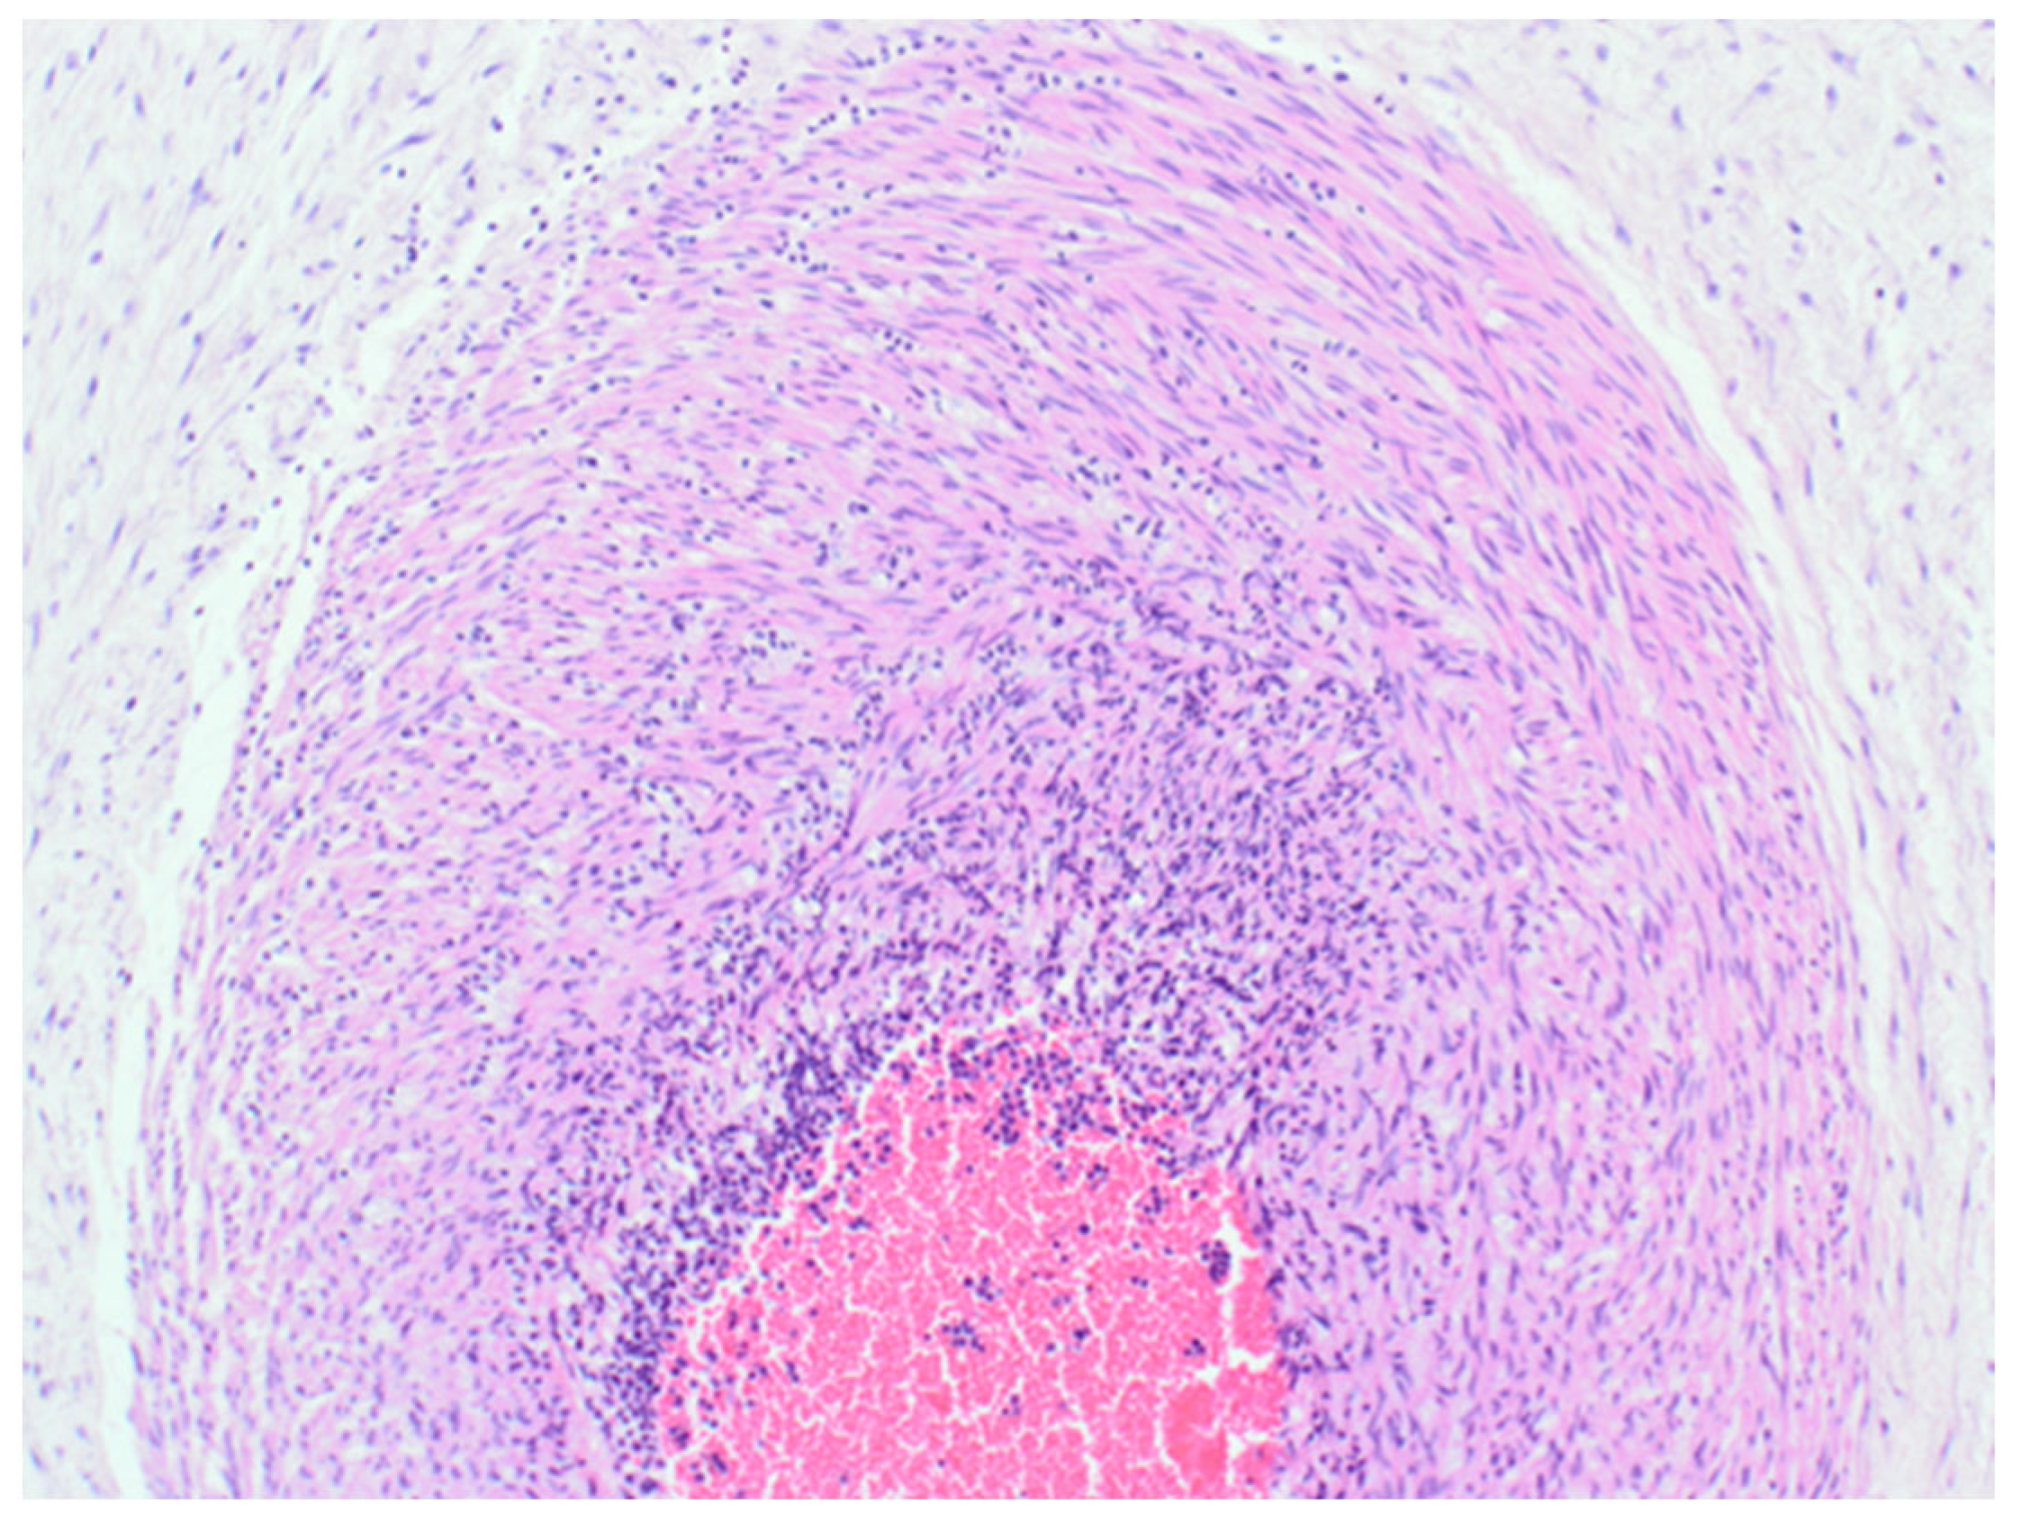

The sample received in the histopathology department was a disc of placenta and membranes with an eccentrically inserted umbilical cord. The placenta trimmed of the membranes weighed 145 mg. The membrane appeared complete and was mostly translucent but with patchy areas of opacity. Microscopy revealed patchy severe acute chorioamnionitis and prominent clusters of Gram-positive filamentous bacteria, which were noted on the surface of the membranes in routine haematoxylin and eosin (H&E) (Figure 1) as well as with Periodic Acid Schiff (PAS) staining (Figure 2). Aggregates of the Splendore–Hoeppli reaction, which are sulphur granules formed from masses of gram-positive bacteria with branching filaments, are also identifiable in Figure 2. The infective organism was revealed to be gram-positive (Figure 3). In this specific case, the microscopic examination indicated the presence of acute inflammation due to an uncommon organism—Actinomyces spp. infection. Sections of the umbilical cord revealed acute inflammation (funisitis), but no organisms were seen in the umbilical cord (Figure 4). During the follow-up visit, the mother did not demonstrate any symptom or sign of infection, her recovery was uneventful, and she remained well during the subsequent reviews.

Figure 4.

Haematoxylin & Eosin (200×). Part of the cross section of the umbilical cord, showing transmural acute inflammatory cell infiltration of the vessel wall consistent with funisitis.